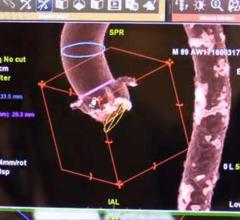

July 13, 2016 — Siemens Healthineers announced that University of Utah Health Care in Salt Lake City is the first ...

Interview with Patricia Dickson, LRT (CT), assistant director, diagnostic and outpatient services, Capital Cardiology ...

An interview with Jonathan Leipsic, M.D., FSCCT, chairman of the department of radiology, St. Paul’s Hospital, Vancouver ...